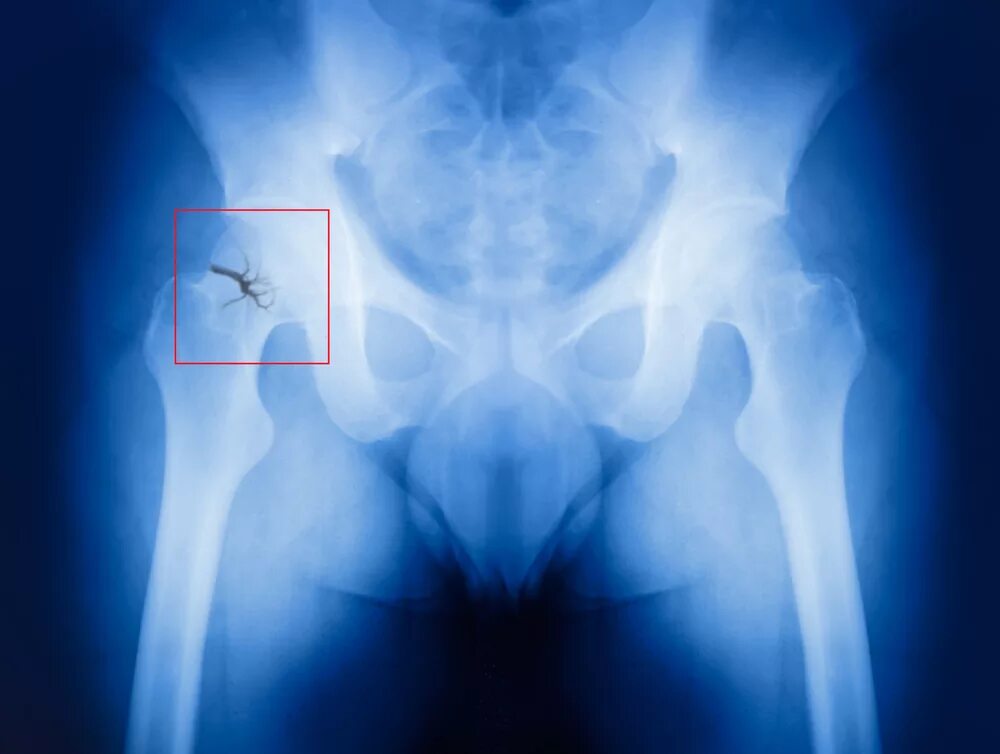

Щель тазобедренного сустава